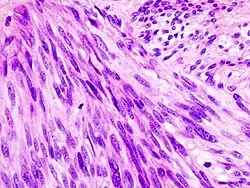

| Histopathologic image of gastrointestinal stromal tumor of the stomach. Hematoxylin-eosin stain. | |

The definitive diagnosis is made with a biopsy, which can be obtained endoscopically, percutaneously with CT or ultrasound guidance or at the time of surgery. A biopsy sample will be investigated under the microscope by a pathologist physician. The pathologist examines the histopathology to identify the characteristics of GISTs (spindle cells in 70-80%, epitheloid aspect in 20-30%). Smaller tumors can usually be confined to the muscularis propria layer of the intestinal wall. Large ones grow, mainly outward, from the bowel wall until the point where they outstrip their blood supply and necrose (die) on the inside, forming a cavity that may eventually come to communicate with the bowel lumen.

When GIST is suspected—as opposed to other causes for similar tumors—the pathologist can use immunohistochemistry (specific antibodies that stain the molecule CD117 [also known as c-KIT] —see below). 95% of all GISTs are CD117-positive (other possible markers include CD34, Discovered On GIST-1 (DOG1),[19] desmin, and vimentin). Other cells that show CD117 positivity are mast cells.